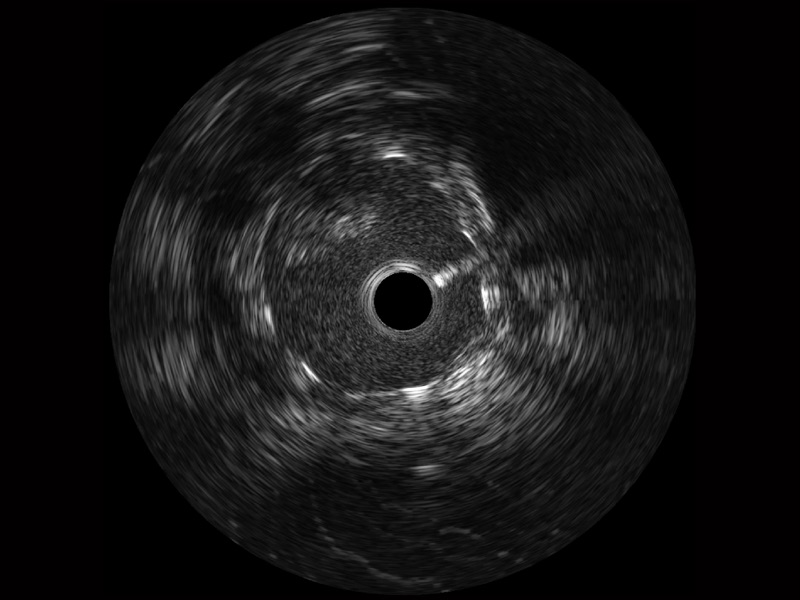

• 乐玩lewin国际宽频IVUS图像

对比传统IVUS导管成像,乐玩lewin国际宽频IVUS图像的近场支架梁显影更细腻,远场中膜外血管仍清晰可辨,兼顾远中近,兼顾分辨力与穿透深度